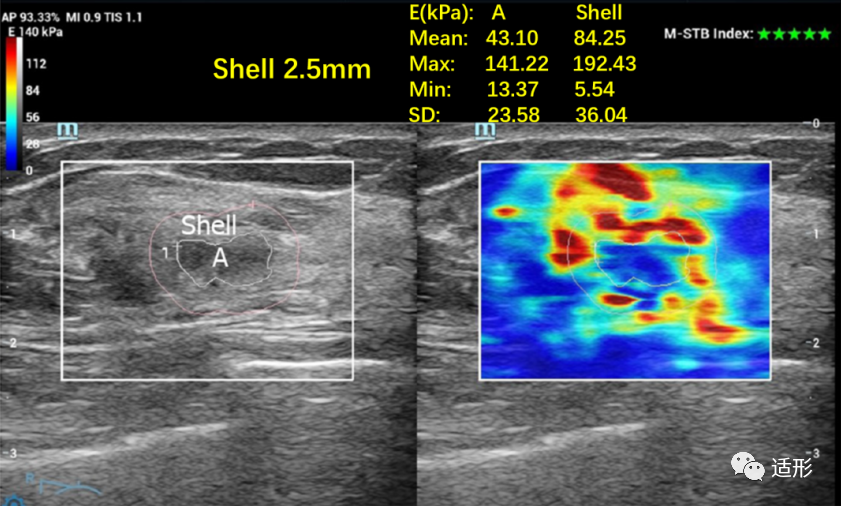

剪切波弹性成像(SWE)能定量的获取病变组织的弹性模量,通常选择平均弹性模量值(Emean)及最大弹性模量值(Emax)鉴别NML的良恶性。但目前不同学者对诊断NML良恶性截断值的选择有一定差异。Park等[2]选取Emean截断值为85.1 kPa。Wang等[3]选取Emax、Emean截断值为.81.07 kPa、63.71 kPa。Ko等[6]选取Emax、Emean截断值为69 kPa、41.6 kPa。这些差异可能是由于不同研究纳入NML样本组成或测量方式不同导致。SWE弹性图上“硬环征”的出现对诊断恶性NML有较高的特异性 (图3)。通过定量的测量病变周围组织(Shell)的弹性模量值也有助于判断NML的良恶性(图4)。Xu等[7]发现恶性NML病灶周围组织的弹性模量值高于良性病灶的周围组织,当病灶周围2.5mm的组织的Emax值以94.62 kPa为截断值时,诊断准确性可达87.44%。

图4 常规超声提示非肿块型病变,剪切波弹性成像可见“硬环征”; 病灶周围2.5mm的组织(Sell 2.5mm) Emax值为192.43kPa。病理:浸润性导管癌[7]